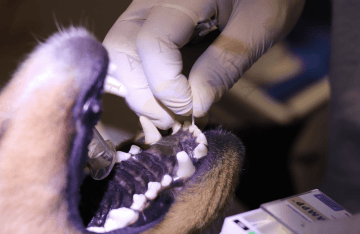

Prvním krokem před jakýmkoliv stomatologickým úkonem u nás je vždy odborní stomatologická konzultace neboli zubní vyšetření. Bez toho nejsme schopni určit typ, rozsah a ani cenu potřebného stomatologického / stomatochirurgického zákroku. Snažíme se k našim klientům přistupovat transparentně tak aby bylo zcela jasno, co všechno je potřebné udělat a kolik to bude stát.

Endodontické ošetření znamená ošetření vnitřního prostoru zubu, laicky řečeno ošetření kořenových kanálků zubu. Je nutné ho provést vždy, když dojde v zubní dřeni k patologickému procesu, tedy zánětu nebo odumření, ať už následkem příliš velkého zubního kazu, nebo úrazu.

Léčba kořenových kanálků (endodoncie) je léčba, která zahrnuje odstranění infikované dřeně z kořenového kanálku zubu, sterilizaci (dezinfekci) kanálku a nahrazení odstraněné tkáně zubním materiálem. Kořenový kanálek je přístupný přes korunku zubu. Jakmile je kořenový kanálek naplněn zubním materiálem, přístup přes korunku je vyplněn (obnoven), aby se zabránilo dalšímu přístupu bakterií do kořenového kanálku. Konečným cílem je zabránit bakteriím v pronikání do zubu. Standartní terapie kořenových kanálků umožňuje domácímu mazlíčkovi zachovat si zub (ačkoli již nežije) a zachovat jeho funkci, protože strukturální integrita zubu byla zachována.